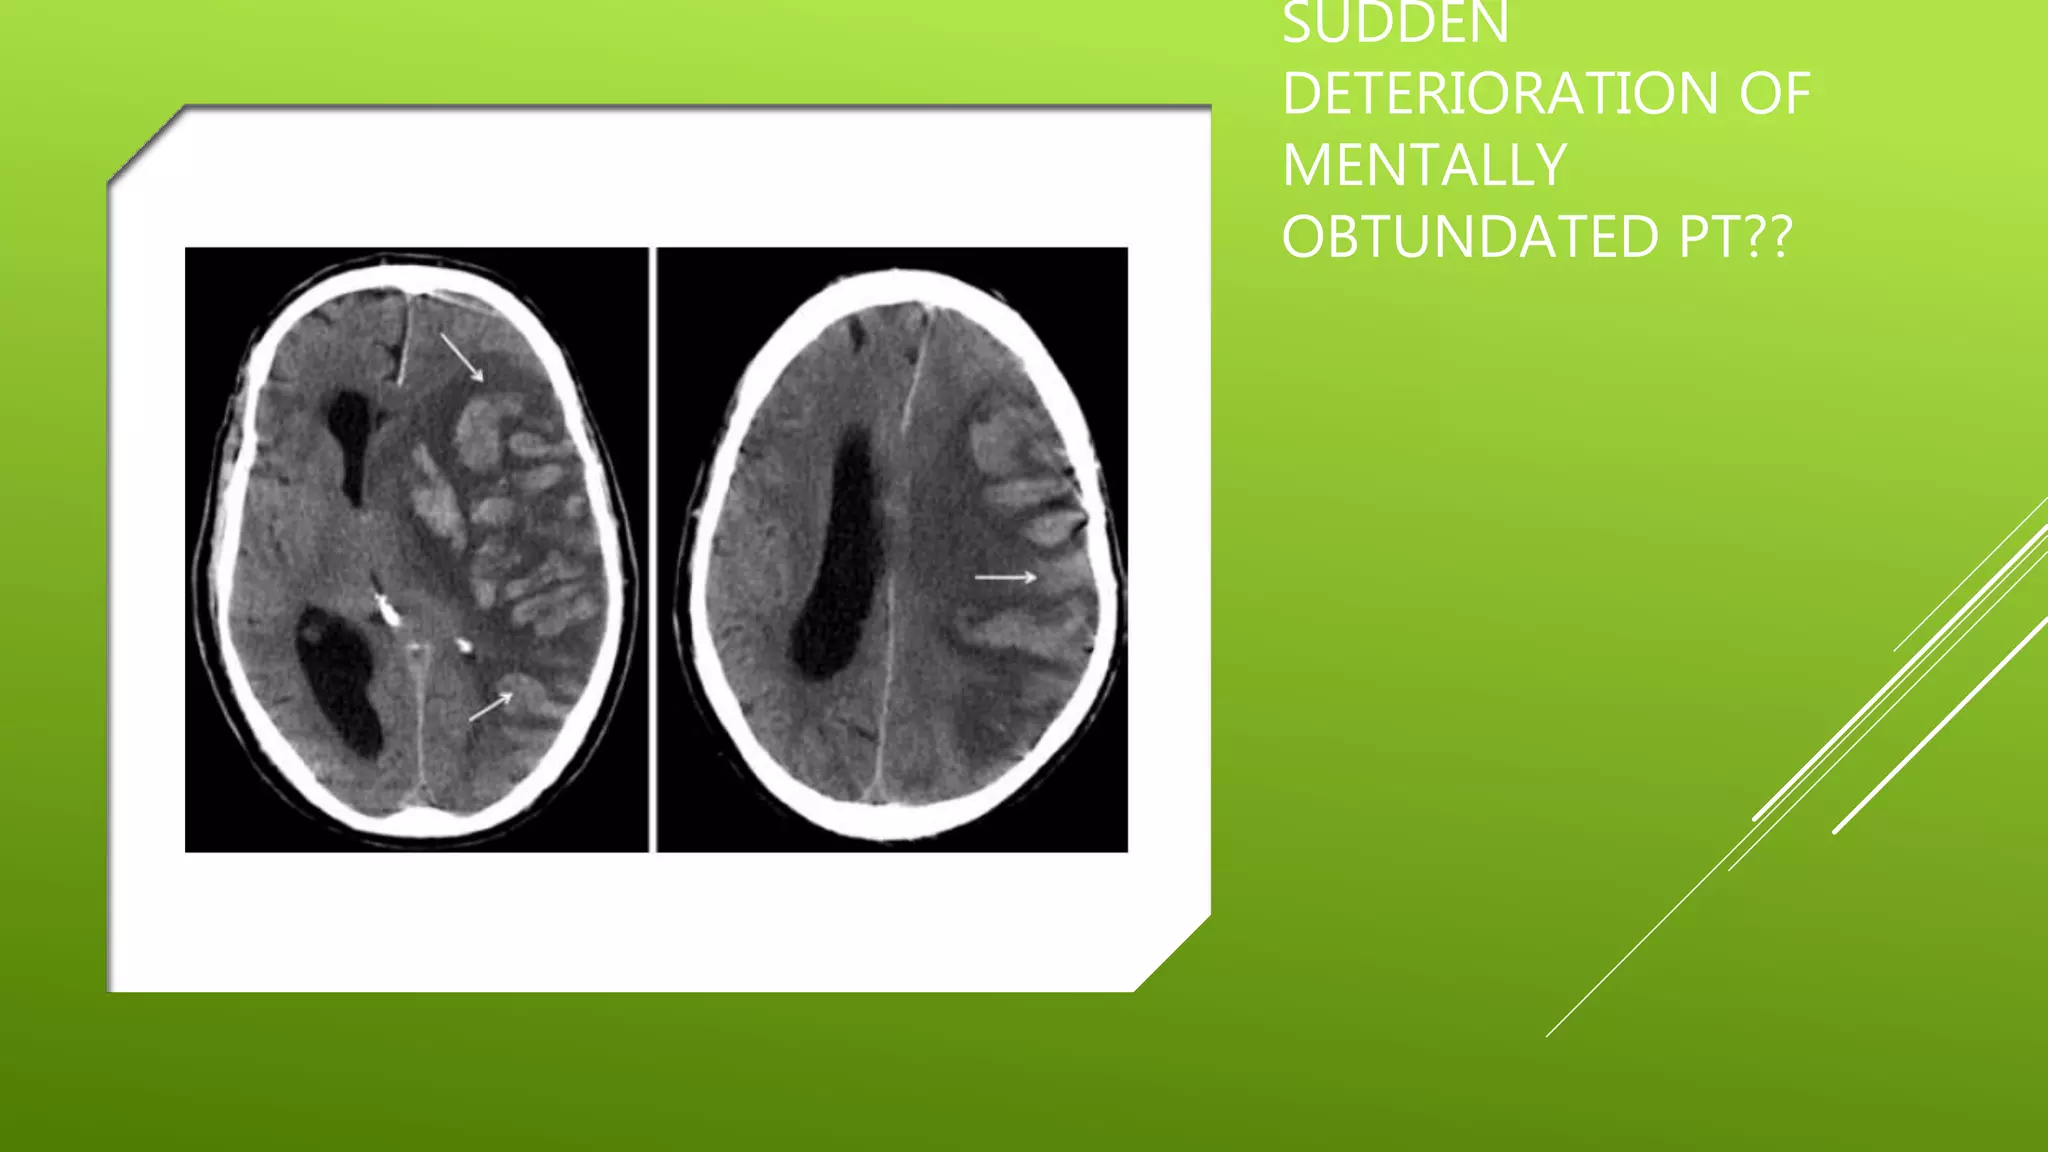

This document contains a series of radiology-related questions and prompts seeking identification and interpretation of various imaging findings, patient presentation details, monitoring values, scoring systems, diagnoses, and management steps. Specific topics include identifying x-ray and CT scan findings, interpreting EKG results, recognizing arrhythmias, assessing intubated and post-surgery patients, and evaluating compliance with treatment plans.